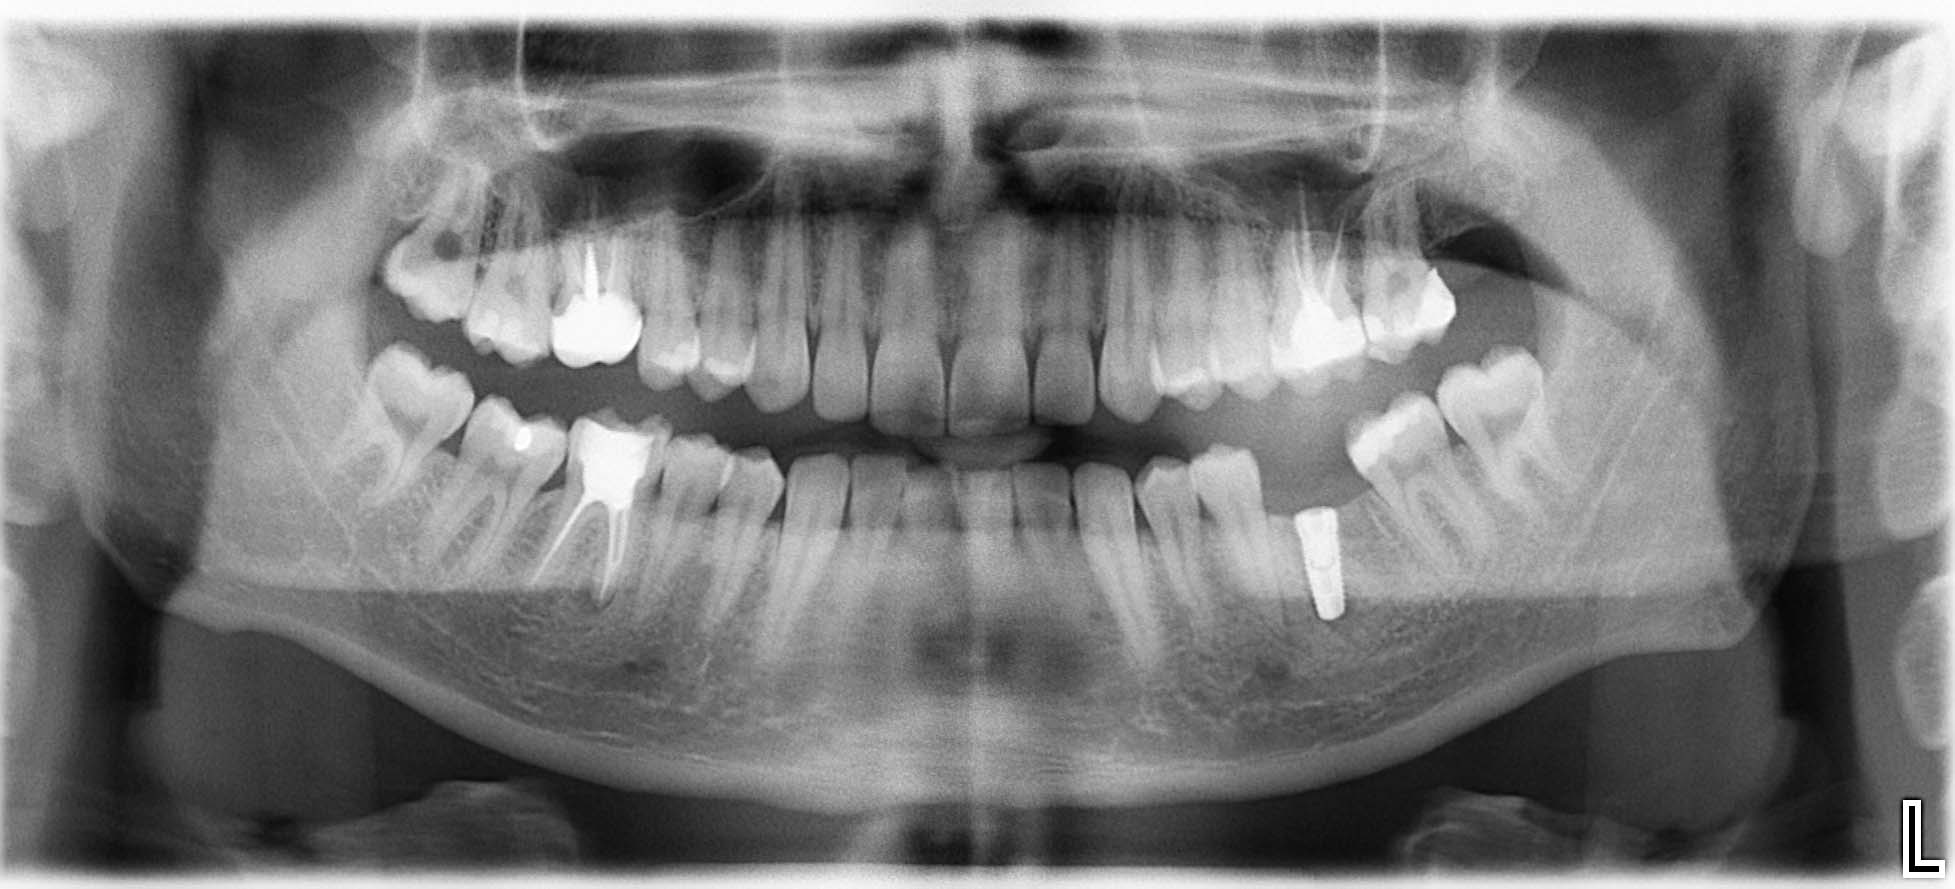

Erfolgreich implantierte Patientenfälle (klinische Fotos)